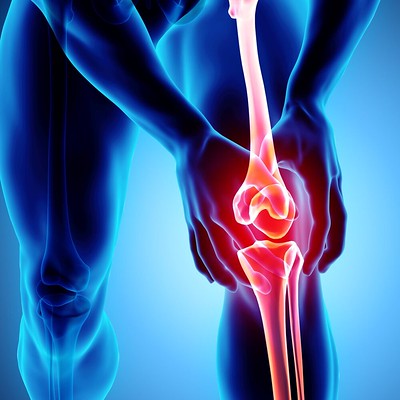

관절염

관절염은 관절에 염증을 일으키는 만성 질환입니다. 골관절염, 류마티스 관절염 및 통풍을 포함하여 무릎 관절에 영향을 줄 수 있는 여러 유형의 관절염이 있습니다. 관절염은 무릎 관절에 통증, 부기 및 뻣뻣함을 유발할 수 있습니다.

반월판 찢어짐

반월판은 무릎 관절을 완충시키는 연골 조각입니다. 찢어진 반월판은 무릎이 갑자기 비틀리거나 회전하는 결과로 발생할 수 있습니다. 이 부상은 운동선수에게 흔히 발생하며 통증, 부기 및 제한된 이동성을 유발할 수 있습니다.

수술 인대 또는 반월상연골 파열과 같은 보다 심각한 무릎 부상의 경우 수술이 필요할 수 있습니다. 진행된 관절염의 경우 무릎 교체 수술이 필요할 수 있습니다.